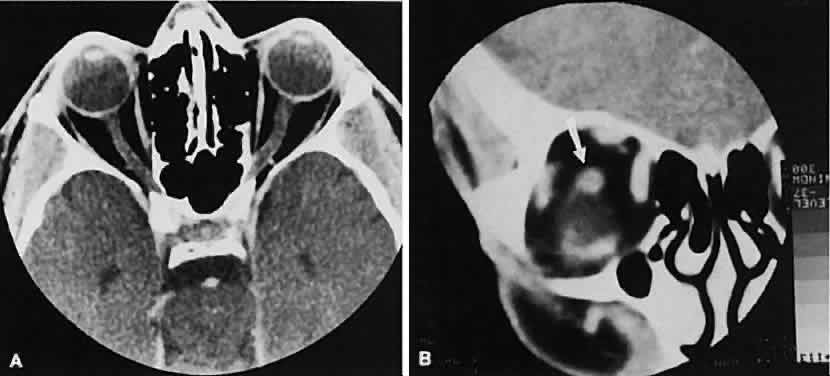

The vascular tumors under consideration are capillary hemangioma, cavernous hemangioma, lymphangioma, and hemangiopericytoma. Capillary hem-angiomas and lymphangiomas are benign infiltrativetumors seen in a pediatric population. Capillary hemangiomas have a homogeneous consistency, display intense uniform contrast enhancement, and do not usually displace any orbital structures (Fig. 12). Phleboliths are a characteristic finding in hemangiomas and, when present, are virtually pathognomonic of this diagnosis.56

Fig. 12. A. Axial view shows an exuberant homogenous soft-tissue mass infiltrating the retrobulbar space and periorbital tissue, typical of large infantile capillary hemangioma. B. Extension (arrow) into the adjacent periorbital tissues can be seen on the coronal view.

Lymphangiomas have a cystic component, which, on occasion, may hemorrhage into itself, accounting for rapid onset of symptoms and clinical/radiographic evidence of mass effect (Fig. 13). In all likelihood, scans require sedation for an adequate study. Thin (1.5-mm) axial views with computer reformatting for coronal views along with contrast enhancement should provide an adequate study.

Fig. 13. Axial view of a lymphangioma that shows a large mixed-density mass with a cystic component.

Both cavernous hemangiomas (Fig. 14) and hemangiopericytomas typically are seen in adults. Their radiographic appearance is similar and shows a well-demarcated, contrast-enhancing mass, although more intense enhancement may be seen with the hemangiopericytoma. The differential diagnosis of a well-demarcated, contrast-enhancing lesion is listed in Table 3.

Fig. 14. Axial (A) and coronal (B) views of a cavernous hemangioma depicted as a hyperdense-enhancing, well-circumscribed mass.